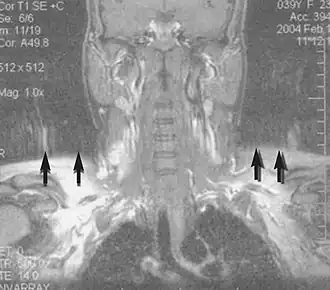

Metal artifacts

Metal artifacts occur at interfaces of tissues with different magnetic susceptibilities, which cause local magnetic fields to distort the external magnetic field. This distortion changes the precession frequency in the tissue leading to spatial mismapping of information. The degree of distortion depends on the type of metal (stainless steel having a greater distorting effect than titanium alloy), the type of interface (most striking effect at soft tissue-metal interfaces), pulse sequence and imaging parameters. Metal artifacts are caused by external ferromagnetics such as cobalt containing make-up, internal ferromagnetics such as surgical clips, spinal hardware and other orthopaedic devices, and in some cases, metallic objects swallowed by people with pica.[3] Manifestation of these artifacts is variable, including total signal loss, peripheral high signal and image distortion (Figs 3 and 4).[1] Reduction of these artifacts can be attempted by orientating the long axis of an implant or device parallel to the long axis of the external magnetic field, possible with mobile extremity imaging and an open magnet. Further methods used are choosing the appropriate frequency encoding direction, since metal artifacts are most pronounced in this direction, using smaller voxel sizes, fast imaging sequences, increased readout bandwidth and avoiding gradient-echo imaging when metal is present. A technique called MARS (metal artifact reduction sequence) applies an additional gradient, along the slice select gradient at the time the frequency encoding gradient is applied.